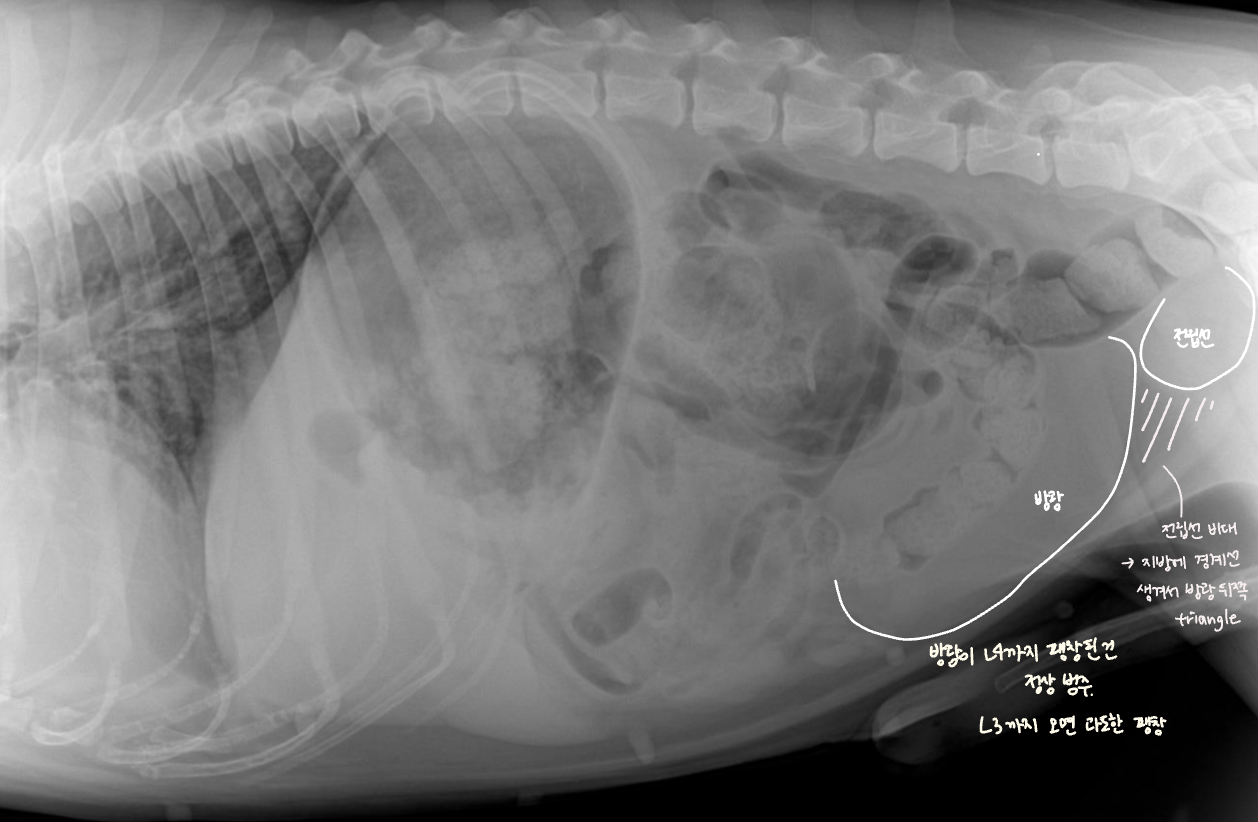

์ ๋ฆฝ์ ๋น๋

| Benign prostatic hyperplasia (BPH) |

|---|

| (๋ฐฐ์ฐ์ง ์์์ง๋ง ์กฑ๋ณด์ ๋ฑ์ฅํ๋ ๋ณ๋ช

.) ์ ๋ฆฝ์ ๋น๋์ ์ํด - ์๋๊ฐ ์๋ฐ๋์ด ๋ฐฉ๊ด์ cranial margin์ด ํฝ๋๋จ. - ์ ๋ฆฝ์ ๊ณผ ๋ฐฉ๊ด ์ฌ์ด์ ์ง๋ฐฉ์ ๊ฒฝ๊ณ๊ฐ ์๊ฒจ ์ผ๊ฐํ ๋ชจ์์ radiolucentํ ์์์ด ๋ํ๋จ. ![]() |